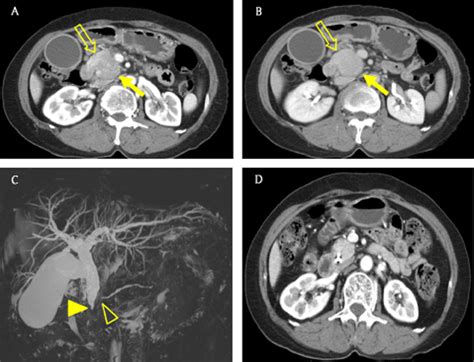

CT scans of pancreatic cancer patient. CT scan imaging at ...

CT scans of pancreatic cancer patient. CT scan imaging at ... from www.researchgate.net

These cancers can invade and press on nerves near the pancreas, which can cause pain in the abdomen (belly) or back. The disease occurs when cells in the pancreas grow, divide, and spread uncontrollably, forming a malignant tumor. A number of types of pancreatic cancer are known. Pain can be a major problem for people with pancreatic cancer. If a pancreatic mass is seen, that raises the suspicion of. Jun 01, 2021 · pancreatic ductal carcinoma (pdac) is a highly lethal cancer, and early detection and accurate staging are critical to prolonging survival. Pancreatic cancer is usually staged following a ct scan. Computed tomography or computerized axial tomography (ct or cat) positron emission tomography ‐ Over 53,000 people in the u.s. For more information about how pancreatic cancer is diagnosed, including imaging tests like mri and mrcp, contact pancan patient services. If a problem is identified or suspected, frequently a computed tomography (ct) scan is performed as the next step in the evaluation; These cancerous cells have the ability to invade other parts of the body. Some clinicians prefer an mri.

Jun 01, 2021 · pancreatic ductal carcinoma (pdac) is a highly lethal cancer, and early detection and accurate staging are critical to prolonging survival. There are three types of ct scan for pancreatic cancer detection. The disease occurs when cells in the pancreas grow, divide, and spread uncontrollably, forming a malignant tumor. The following imaging tests may be used to find out if the bladder cancer has spread and to help with staging. These cancerous cells have the ability to invade other parts of the body.